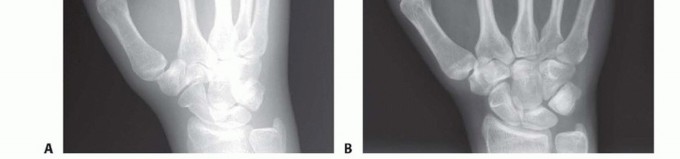

FIG 5 • A. Missing fourth metacarpal shaft and base after gunshot wound. Patient had tenuous dorsal skin. Metacarpal head temporarily stabilized with buried pins from fifth metacarpal. B. Once the soft tissues stabilized, the metacarpal was grafted from the iliac crest and stabilized with plate and screws to the hamate. C. Dorsal sensory branch of the ulnar nerve travelling through the center of the wound on a different patient. Grossly contaminated wounds, or those with tenuous soft tissues, may be best managed initially with limited fixation until more definitive fixation can be performed (FIG 5A).Bone grafting may also need to wait until the soft tissues have stabilized (FIG 5B).The need to address nerve, vessel, or tendon injuries may also affect the approach (FIG 5C).